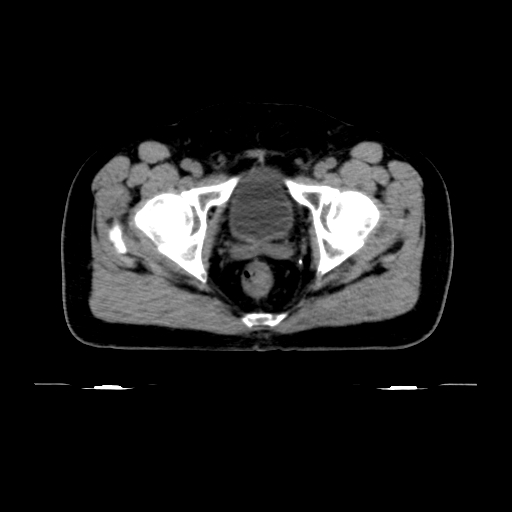

Planning CT Images

Treatment Plan Images